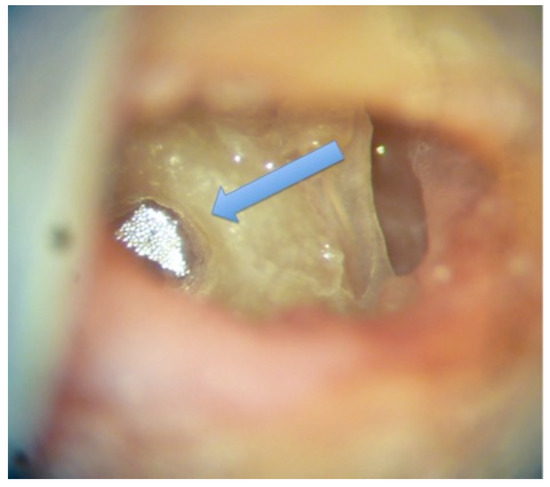

A standard bilateral mastoidectomy, including a facial recess approach to access the round window, was performed on each head. The edge of the round window niche was slightly drilled to have direct access to the round window membrane. A 1 mm2 reflector for the laser beam of the velocimeter was placed on the round window on one side (Figure 1).

Figure 1. Reflector on the round window (white color). The blue arrow shows the round window.